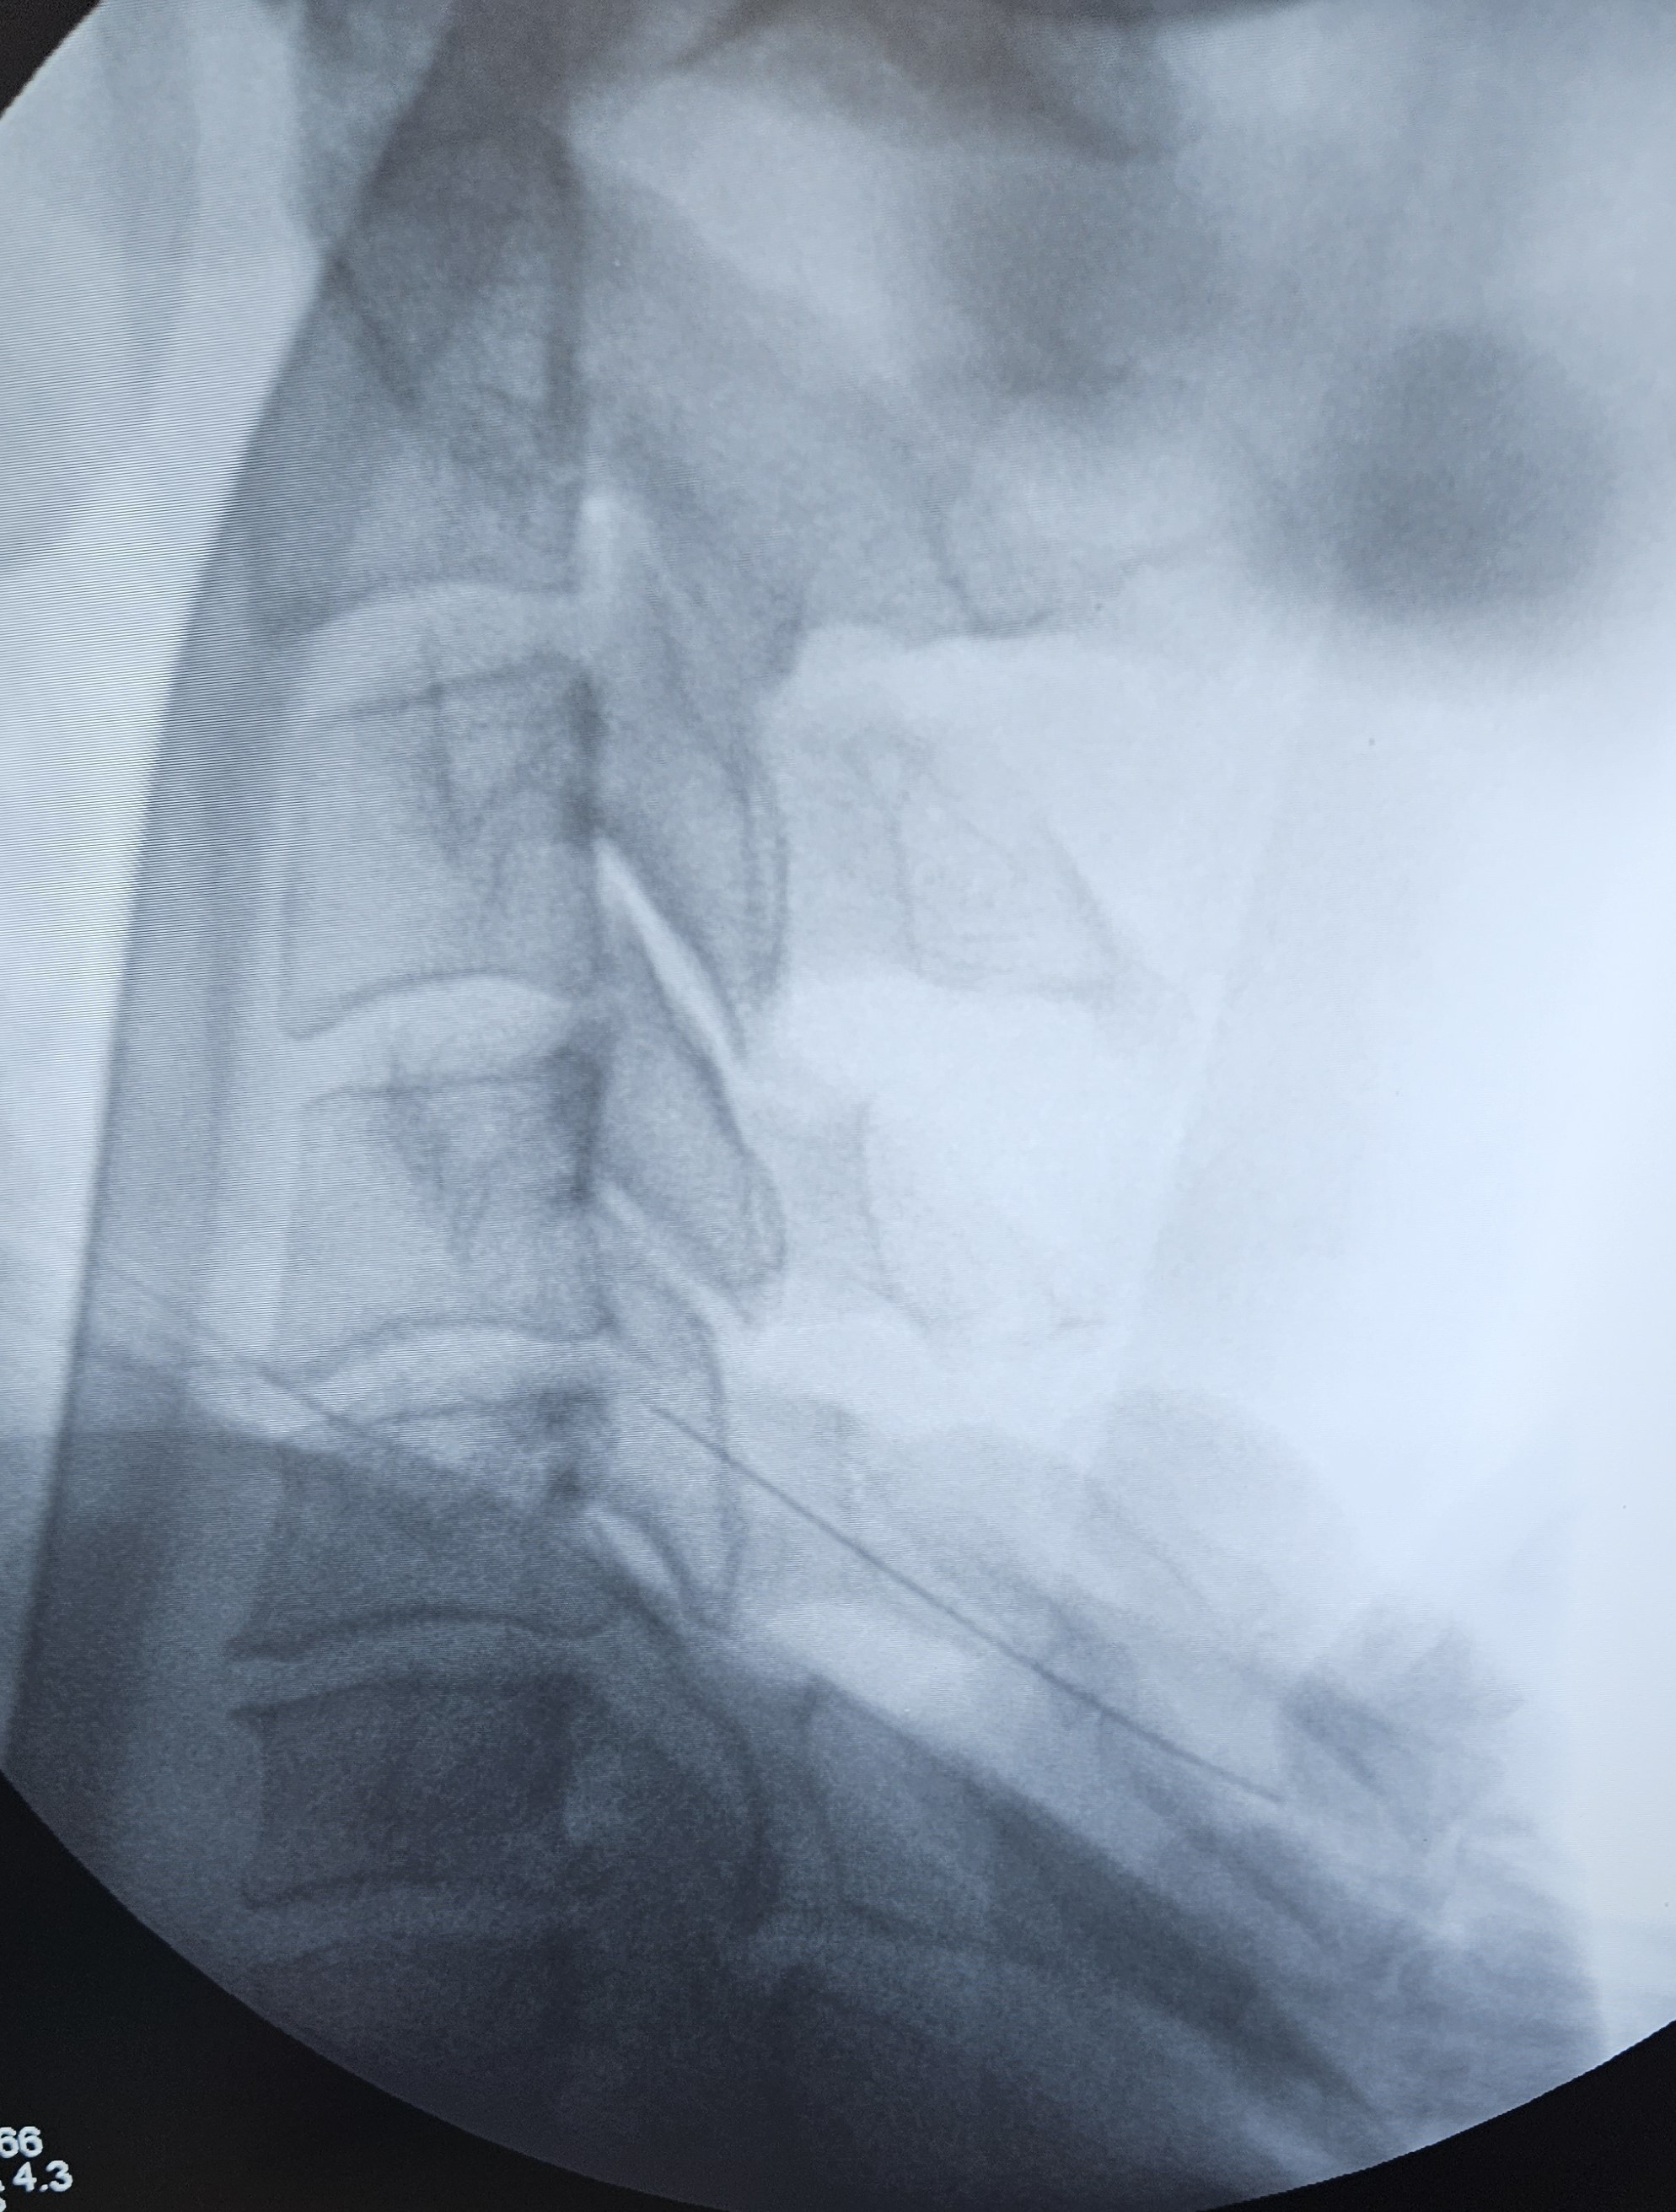

Με τον ασθενή σε πρηνή ή πλάγια κατακεκλιμένη θέση, χορηγείται τοπική αναισθησία για να μουδιάσει το δέρμα. Ο ιατρός εισάγει μια λεπτή βελόνα στο σημείο εντοπισμού των μέσων νευρικών κλάδων κάτω από ακτινοσκοπική καθοδήγηση. Ακολουθεί κινητικός και αισθητικός ερεθισμός και επί κατάλληλων ενδείξεων, η βελόνα συνδέεται με την πηγή ενέργειας, αφού εγχυθεί μικρή ποσότητα αναισθητικής ουσίας, για να μην δυσφορεί ο ασθενής κατά τη διάρκεια της παρέμβασης. Η ίδια διαδικασία ακολουθείται σε όλα τα επίπεδα που χρήζουν κατάλυσης.